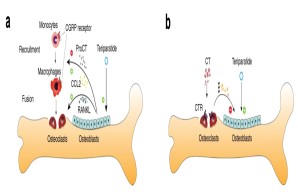

Cellular communication mechanisms in osteoimmunology

The interaction of bone and immune cells plays a major role in many diseases. This interaction is not only important in normal or pathological bone remodeling (i.e., osteoporosis), but also controls degenerative (e.g., osteoarthritis) and regenerative processes (e.g., fracture healing). In our work, we therefore characterize the influence of specific immune cells on bone remodeling, joint degeneration and bone healing, and investigate to what extent immunomodulatory substances are suitable for the treatment of skeletal diseases.

Fig.: Interaction of bone cells with immune cells after osteoanabolic teriparatide therapy. (a) Teriparatide induces procalcitonin (ProCT) expression in osteoblasts, which impairs the recruitment of osteoclast precursors (i.e., monocytes and macrophages) to the bone surface, thereby inhibiting bone resorption. (b) Circulating calcitonin (CT) impairs the osteoanabolic effect of iPTH based on tonic inhibition of bone formation, presumably via osteoclasts. Modified from Baranowsky et al, Bone Research 2022.